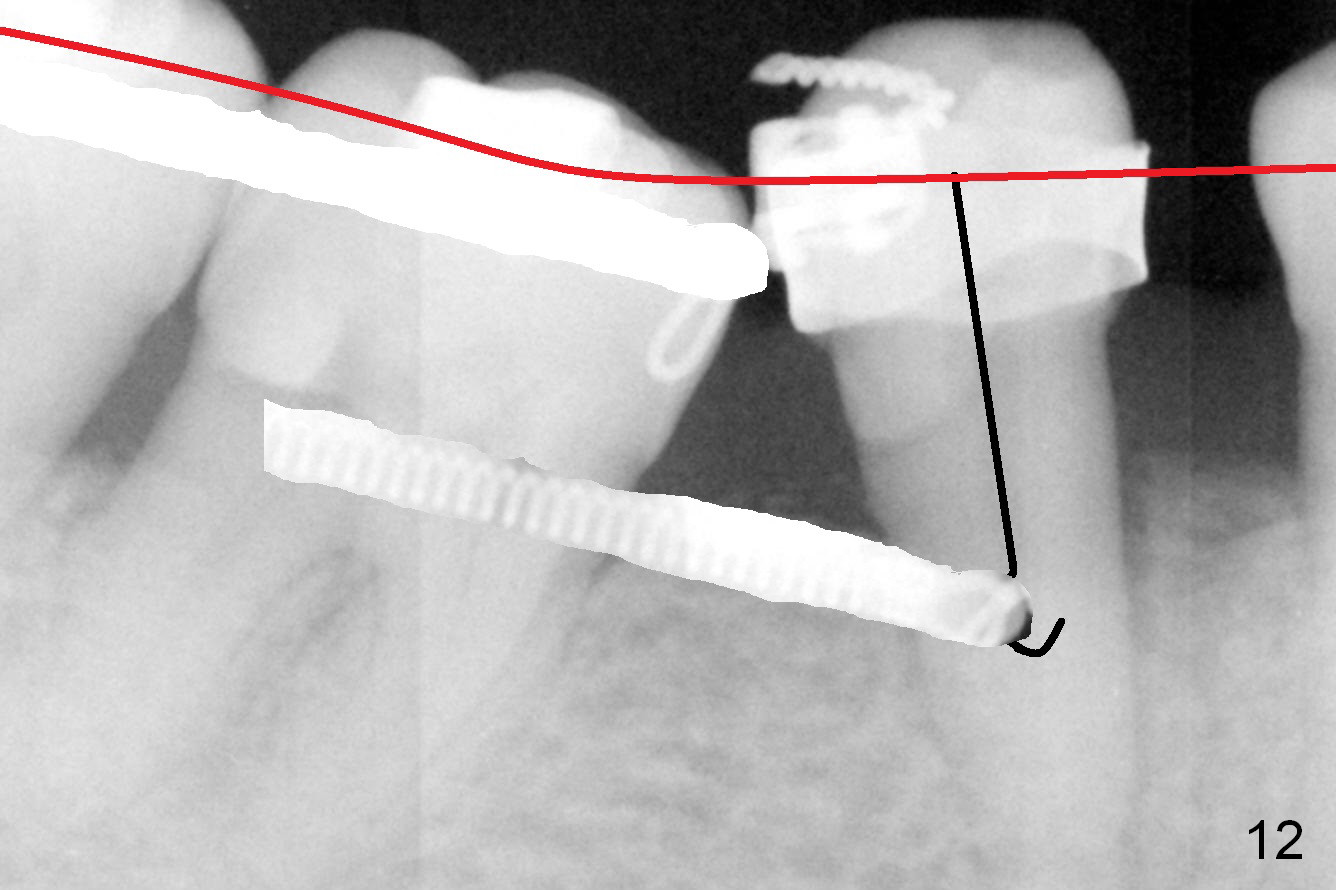

A 47-year-old lady has lost the lower right 1st molar for long time; with reduction of the buccolingual width (Fig.1) and mesiodistal width (Fig.2,3). With regional orthodontic appliance (Fig.4) for 3 months, the tooth #29 has started being distalized (Fig.5). One month and a half later, the tooth #26 starts to shift labially. Power chains and then closed coil spring are placed between #29 and 32. #29 distalization is slow (Fig.7) with closure of the diastema between #31 and 32 (Fig.8, as compared to Fig.1,3). Seven months post banding, a 10 mm miniimplant is placed distobuccal to the tooth #32 (Fig.6); the same 12-mm closed spring is stretched distal by ~ 6 mm (Fig.8 between arrowheads). Two months later, #29 is more distalized (Fig.9 tilted) with bone deposit mesially (*) and coronally (^). A .018' stainless steel wire is installed with an open coil spring placed between #28 and 29 (Fig.10 (^),11). Note #29 rotation (Fig.11). To solve the tilting, a power hook (Fig.12 black) will be clamped to a .016x.016 wire (red), while the closed spring is lowered and attached to the power hook (Fig.12 white). Take photos after removing the existing wire occlusally to show the alveolar width change. When the wire is placed, make sure that the distal wings of #29 bracket is fully engaged to reduce the tooth rotation. Make occlusal adjustment on #31 and 32 to reduce anterior open bite.